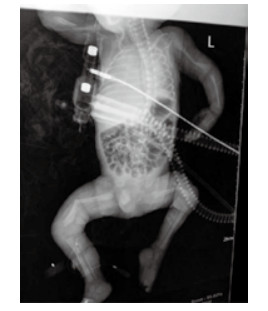

1 资料与方法孕妇20岁, 因“停经38周、阴道流液伴下腹坠胀1 h”于2015年9月10日23:45入住浙江大学明州医院产科。孕妇平素月经规律, 停经3个月在社区医院建卡定期产前检查, 停经17周产前筛查低风险, 停经20周自觉胎动无异常, 停经25周社区医院超声检查未见异常, 停经32周再次社区医院超声示胎儿臀先露, 羊水指数(AFI)22.5 cm, 余未见异常。既往体健, 无遗传病家族史, 孕期无病毒感染及放射线等不良接触史。入院查体:生命体征平稳, 发育正常, 营养可, 心肺听诊无异常; 腹膨隆, 宫高33 cm, 腹围99 cm, 胎位LSA, 胎心率140次/min, 先露臀、棘上3 cm, 宫口容1指, 羊水淡黄色。入院超声检查:宫内孕, 单活胎, 臀位, 双顶径9.3 cm, 股骨长7.4 cm, 头围33.4 cm, AFI 9.6 cm。因“臀先露”于9月11日02时09分剖宫产娩出一男活婴, 手术顺利, 重2 550 g, 身长50 cm, 面部外观未见异常, 四肢瘫软外翻、骨细小有骨擦感, 阴茎短小、睾丸未降, 1分钟Apgar评3分, 立即清理呼吸道、行气管插管气囊加压及呼吸机辅助呼吸等抢救, X线片示双侧股骨中下段明显成角, 左肱骨下段轻度成角, 右肱骨中下段不连续, 断端错位并轻度重叠移位(图 1)。新生儿抢救1 h后无效死亡。死亡原因:新生儿重度窒息, 新生儿骨软骨发育异常并多发性骨折, 死亡原因不明确申请尸检。

| 图 1 X线显示新生儿双侧股骨及左侧肱骨成交, 右侧肱骨骨折, 四肢骨及肋骨发育细小、骨密度减低 |

新生儿尸检报告:(1)成骨不全病(脆骨病); (2)双侧肱骨、双侧股骨病理性骨折; (3)双侧肘关节、腕关节、膝关节脱位, 桡、尺骨骨膜分离, 骨形态细小; (4)颅骨发育不全; (5)头皮帽状腱膜下出血; (6)心脏、大血管、双肺无畸形。

X线检查在成骨不全诊断方面有重要价值, 表现为骨密度降低、骨皮质变薄、四肢短特别是下肢多发性骨折, 对超声或临床评估不排除OI患儿可行辅助性诊断; 对有OI患病或生育史者再次妊娠可通过培养绒毛成纤维细胞分析胶原合成对成骨不全进行产前诊断[21]。COL1A1和COL1A2基因突变检测是最直接证实该病分子基础的方法, 但仅适用于孕前已明确先证者具体突变类型的孕妇[22]。